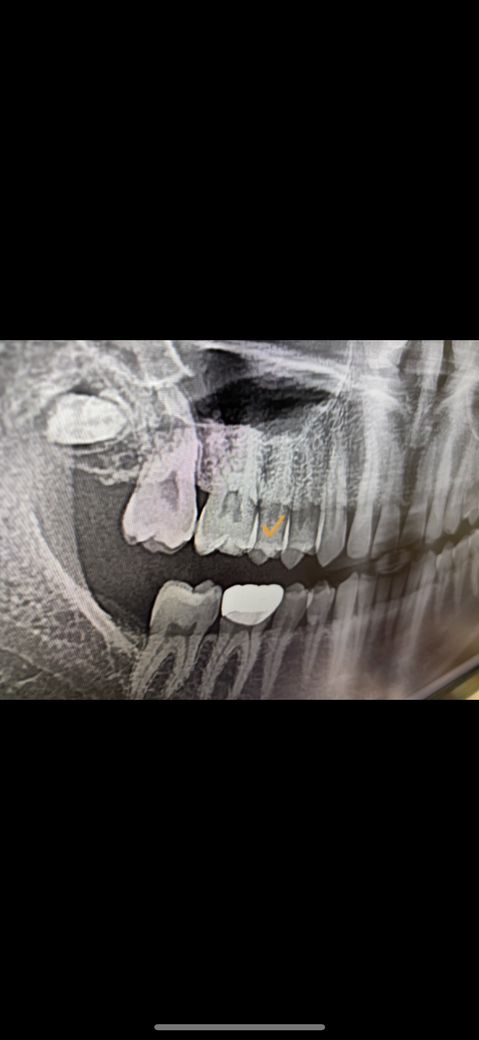

체크한부분 이빨과 이빨 사이에 충치생겼는데

많이썩었나요? 치료를 빨리해야겠죠??,,,,

• 1번 째 사진

방사선사진으로만 봤을 경우에는 충치가 커보이지는 않습니다. 충치가 있다면 충치를 치료하는것이 좋습니다. 충치가 있는 부위에 이물질이 남아 있게 되면 충치가 더 진행될수 있기 때문입니다.

파노라마 사진으로는 정확히 보기가 어렵고 작은 사진을 찍어 보면 치아 사이에 충치확인이 더 정확합니다.

위 사진은 인접면 충치를 정확히 볼 수 없고 치근단사진 중 교익방사선 사진을 통해서만 판독이 가능합니다.